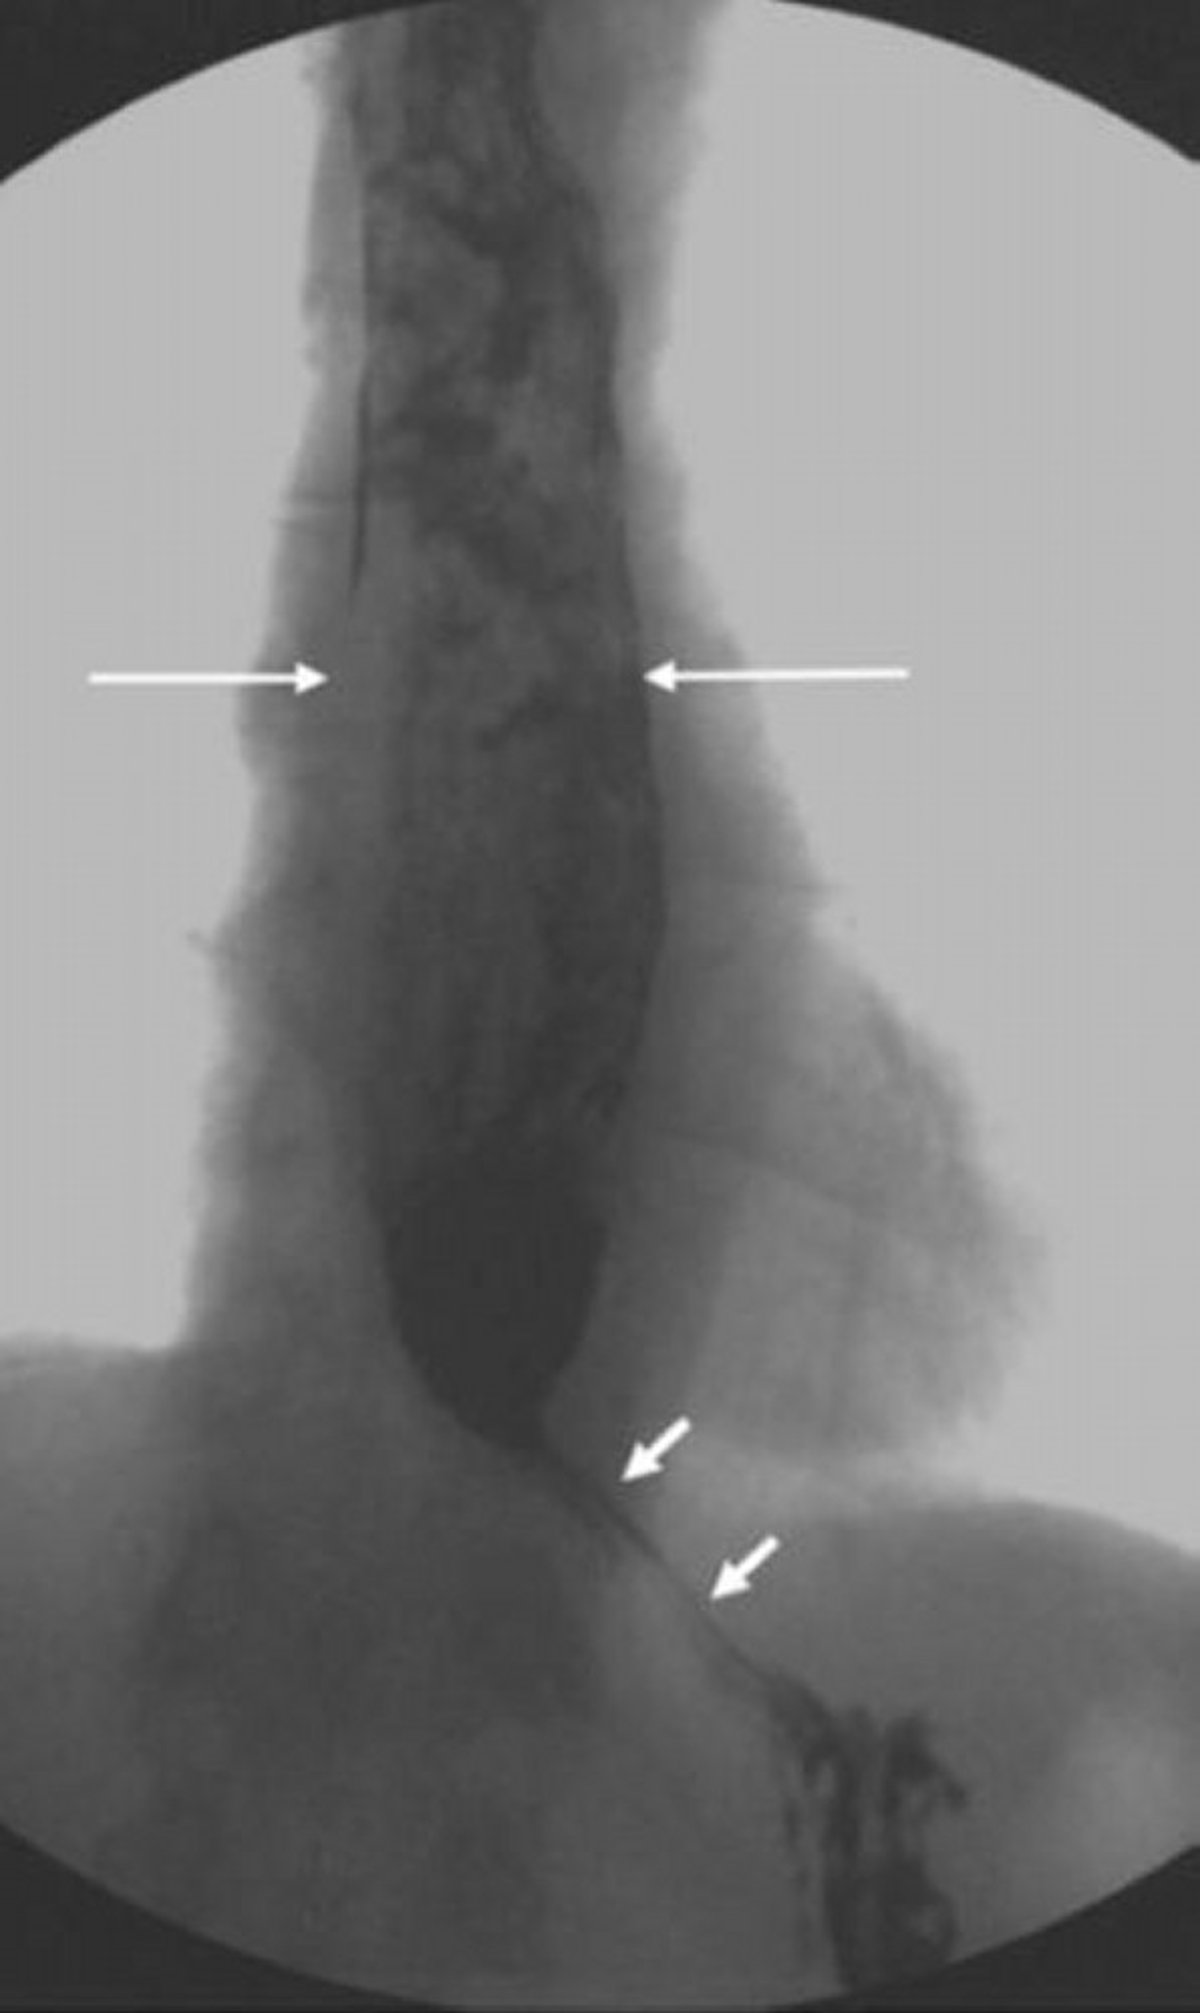

Barium Swallow Showing Dilated Esophagus with Narrow and Beaklike Appearance at Lower Esophageal Sphincter

This image shows achalasia with proximal esophageal dilatation and incomplete lower esophageal sphincter relaxation. Note the inhomogeneous appearance of the material within the dilated esophagus due to undigested food that did not pass into the stomach (long arrows). In severe achalasia, only small quantities of contrast medium are able to pass through a beaklike esophagogastric junction (short arrows).